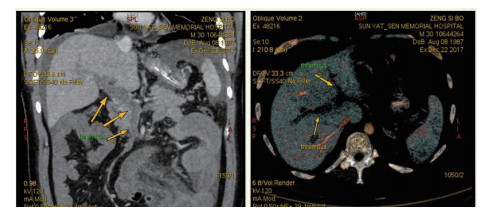

| 图 1 全腹CTA(2017-12-22):门静脉及肠系膜上静脉血栓形成 |

1 资料与方法患者男,30岁,因“腹胀、腹痛6 d,高热1 d”于2017年12月11日由广州南沙区中心医院转诊收入中山大学孙逸仙纪念医院全科医学科。患者本次起病前无明确病因或明显诱因。患者以左上腹轻微胀痛起病,进行性加重。南沙区医院查血常规:白细胞14.27×109/L,血小板50×109/L,中性粒细胞比例74.5%,嗜酸粒细胞1.02×109/L,嗜酸粒细胞比例7.2%。全腹CT+CTA提示:门静脉左右主干及其小分支栓子形成。后在3 d内连续复查血常规,提示血小板进行性下降,由50×109/L相继降至35×109/L、18×109/L;(嗜酸粒细胞计数及比例未能提供),并出现高热(体温39.5℃),因病情危重,遂转诊本院。入院时患者精神疲乏、高热,腹部胀痛难忍,伴有咳嗽。查体:体温38.6℃,心率87次/min,血压102/76 mmHg,指尖血氧饱和度90%~91%。双肺呼吸音粗,双肺均可闻及小水泡音。腹部稍膨隆,叩诊鼓音,左上腹及脐周轻压痛,无反跳痛。听诊肠鸣音减弱,约1~2次/min。当天查血常规示白细胞11.85×109/L,血小板23×109/L,中性粒细胞比例58.1%,嗜酸粒细胞3.5×109/L,嗜酸粒细胞比例29.5%。凝血常规提示:PT 15.9S,PTA 51.1%,PT/R 1.39,Fbg 1.59 g/L,PTINR 1.39,APTT 35.2 s,D-二聚体114.36 mg/L FEU(参考值范围0~0.55 mg/L FEU)。胸部+全腹部CT+CTA示“门静脉主干及左、右支、肠系膜上静脉近端栓子形成;腹主动脉及左侧髂总动脉小附壁血栓;左肺上叶尖后段、左肺上叶下舌段、右肺中叶及双肺下叶炎症;乙状结肠两段节段性管壁增厚,建议排外占位性病变;腹水、盆腔积液,大网膜炎性病变可能性大”。每日复查血常规,发现血小板进行性下降,最低至15×109/L(参考值范围125~350×109/L),嗜酸粒细胞计数及比例进行性升高,分别达到8.07×109/L(参考值范围0.020~0.52×109/L)和51.1%(参考值范围0.4-8.0%)。每日复查凝血常规亦提示凝血指标不断恶化,纤维蛋白原最低降至0.63 g/L。在予禁食、“美平(美罗培南)”抗感染、输注纤维蛋白原及血小板、维护水电解质平衡及营养支持的积极治疗的同时,还积极完善了以下检查寻找病因:①血液系统方面:血浆鱼精蛋白副凝实验:阳性(+);凝血功能实验:PT 15.5S↑,PTA 47.8%↓,PT/R 1.35↑,PTINR 1.36↑,APTT 40.4 s↑,AT-Ⅲ 57.7%↓,F-VII 32.8%↓,F-Ⅷ 68.1%↓,F-X 68.0%↓,F-XII 24.0%↓;纤维蛋白降解产物:381.4 mg/L↑;血栓弹力-血小板图:R时间10.3 min↑;角度18.5度↓;最大血块强度13.2 mm↓;MA(ADP)值5.6 mm↓。骨髓病理学:嗜酸性粒细胞增多(43%),巨核细胞减少(7个)。慢淋/淋巴瘤表型分析:获取和分析细胞数5.0万;粒细胞区百分比82.6%;淋巴细胞区百分比9.4%;单核细胞区百分比2.0%;CD45dim细胞区百分比1.3%;有核红及细胞碎片区域百分比4.6%。ETV6/PDGFRB融合基因、FIP1L1/PDGFRA融合基因(—)。骨髓细胞学病理结果:符合嗜酸细胞增多症;②消化系统检查:大便细菌培养鉴定及药敏提示无志贺、沙门菌生长,有真菌生长;大便难辨梭菌毒素检测(—);粪便找寄生虫、找阿米巴、寄生虫七项均为(—);消化肿瘤系列提示CA-125 244.8 U/mL↑;腹腔穿刺术穿出“血性腹水”,腹水CA-125 1006.0 U/mL↑,腹水找癌细胞(—);复查腹部CT+CTA:乙状结肠两段节段性管壁增厚,建议进一步检查;排外占位性病变;遂行PET-CT:提示全身未见明确恶性征象。行电子结肠镜示:内镜诊断:(1)回肠末段炎症;(2)乙状结肠炎症;(3)内痔。钳取组织送病理,提示:标本①(回肠末端)黏膜组织呈慢性炎,伴糜烂,一些嗜酸性粒细胞浸润(约35个/HPF);②(乙状结肠)黏膜组织呈慢性炎,伴糜烂,个别嗜酸性粒细胞浸润(约4个/HPF)。③风湿免疫系统方面:免疫八项、风湿四项:C反应蛋134.0 mg/L,余未见异常;总IgE 170 IU/mL↑;抗ENA抗体、狼疮两项、血管炎两项、免疫球蛋白G4、抗心磷脂抗体三项均为阴性;④其他感染病原学检查:乙肝、肝炎系列、性病三项、痰找抗酸杆菌、T-spot实验、流行性出血热、登革热抗体、登革热病毒NS1抗原、外斐氏试验、肥达氏试验、痰结核培养、骨髓培养、血液细菌、血液厌氧菌培养均为阴性。经过上述检查,初步考虑“特发性嗜酸性细胞增多症”,于12.15开始予“甲泼尼松龙40 mg静滴, 1次/d”及“低分子肝素0.6 ml皮下注射, 1次/d”抗炎抗凝治疗。患者病情及检验指标有所好转,热退、腹胀减轻,血常规提示血小板升至49 ×109/L,嗜酸粒细胞计数和比例均下降至正常,凝血常规提示D-二聚体降至47.90 mg/L FEU。但12-22患者自行进食多量米饭后突发腹胀痛较前加重,急查血常规提示白细胞升至21×109/L,血小板再次下降至15×109/L,D-二聚体升至97.28 mg/L FEU,全腹CTA提示“门静脉主干及左、右支、肠系膜上静脉近端新发栓子形成”,遂于当日转至ICU予“尿激酶20万U+肝素钠1250 U”溶栓治疗后予“低分子肝素0.6 ml皮下注射, 1次/12 h”序贯抗凝治疗。后患者病情渐渐稳定,至2018-1-18患者在“甲泼尼松龙12 mg口服, 1次/d”及“立伐沙班20 mg口服, 1次/d”的维持治疗下,血小板、嗜酸粒细胞计数及纤维蛋白原均回复正常,D-二聚体下降至3.52 mg/L FEU。但遗憾的是,此时患者再次进食大量米饭,约1 h后突发腹痛、气促,急行胸片+腹平片提示:“双侧膈下游离气体,考虑胃肠道穿孔可能;双下肺少许炎症,少量胸腔积液;腹部多量积气伴肠腔扩张”。遂即送手术室行全麻下“腹腔镜探查+坏死空肠切除+大网膜切除+肠系膜上动脉探查+空回肠双腔造口术”,术后病理提示标本①(大网膜)脂肪组织,部分坏死,合并慢性炎,伴一些中性粒细胞浸润,较多泡沫样组织增生,未见明确血栓,未见恶性改变。②(部分空肠)肠壁组织,部分肠壁全层坏死,合并慢性炎,肉芽组织增生,未见明确血栓,未见恶性改变。免疫组织化学:CD38浆细胞(+)、IgG(+)、IgG4(﹣)。术后继续予“立伐沙班10 mg/d”和“甲泼尼松龙8 mg/d”口服治疗,并于2018.2.4停用“甲泼尼松龙”。2.28复查全腹CTA,仍可见“脾静脉新发血栓,门静脉及肠系膜上静脉血栓较前好转”。3.20行空回肠双腔造瘘管泛影葡胺造影术提示“双腔造瘘管通畅,右中下腹小肠蠕动尚可,结肠各段及直肠通畅,未见对比剂外漏征象”。但患者合并了严重的短肠综合征,致严重低钾低钠血症和继发的代谢性脑病,病情再度转危。继续纠正电解质紊乱、补充营养,最终病情好转后于4.11行“造瘘口回纳修补术”。随访半年,患者仍口服“立伐沙班10 mg/d”抗凝治疗,复查血常规、凝血常规等各项指标均正常,但营养状况较差。